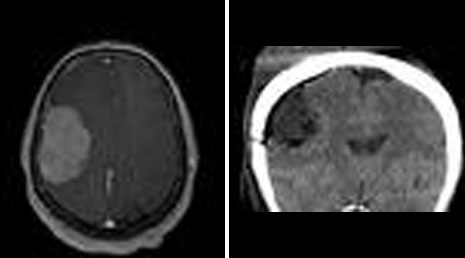

24. Convexity meningioma.

25. Cranial gunshot.